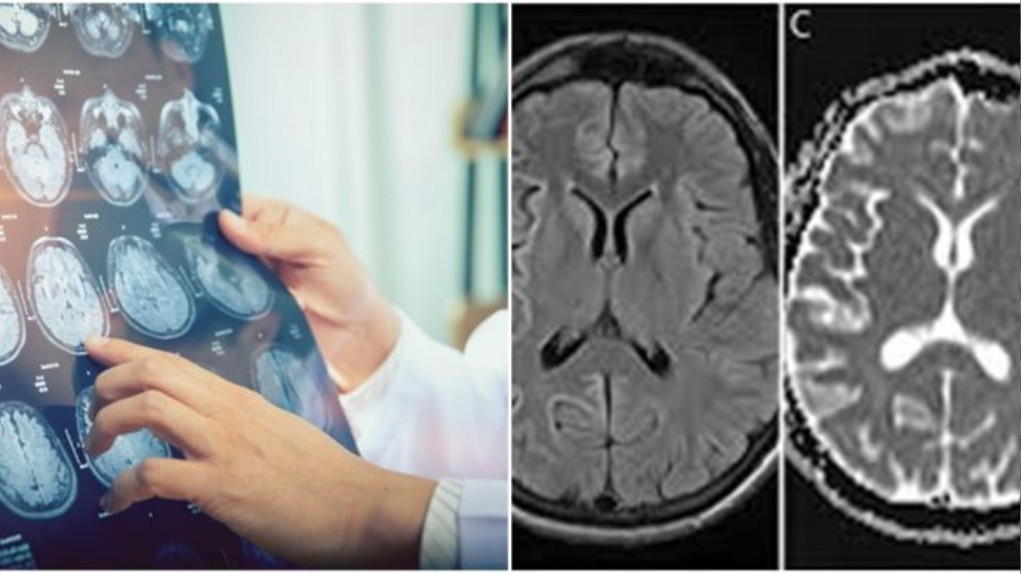

- Chụp MRI:

Thủ thuật xét nghiệm hình ảnh này sử dụng sóng vô tuyến điện và từ trường để tạo ra hình ảnh cắt ngang của đầu và cơ thể. Chụp MRI đặc biệt hữu ích trong việc chẩn đoán các rối loạn não vì hình ảnh của chất trắng và chất xám của não sẽ được thể hiện rõ.